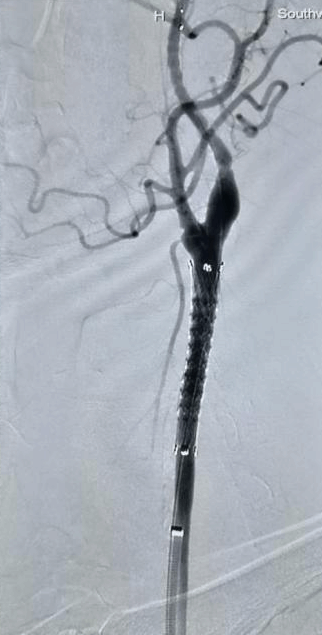

血管狭窄性疾病诊疗技术: